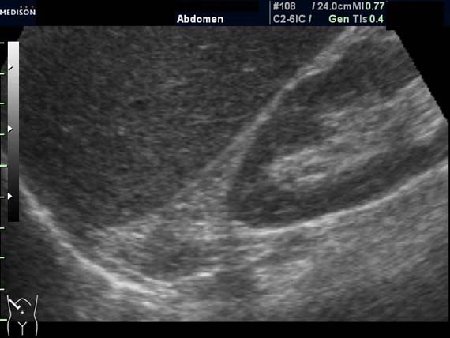

Женщина 50 лет. Жалоб нет. Обследование перед поездкой в санаторий по поводу дисфункции гепатобилиарной системы.

Случайная находка в нижней трети левой почки (не в полюсе, а по задне-медиальной поверхности).

Образование в левой почке

Согласен. Именно с таким диагнозом (ангиомиолипома) отправил на КТ. Особенностью случая ИМХО является заметный "выход" образования за контур почки (на 2/3 объема).